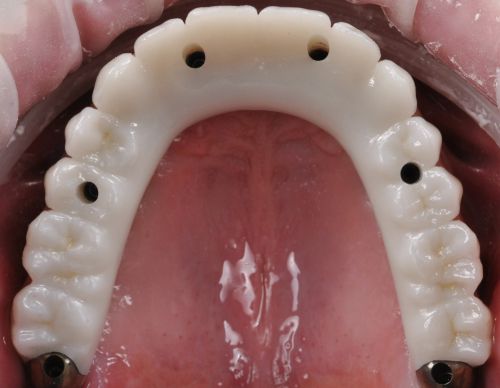

Wykonana praca protetyczna:

- most pełnołukowy na sześciu implantach

- korony na zęby własne w łuku dolnym

- korony na implantach w miejscach braków zębów

- odbudowa flow-injection zębów dolnych przednich